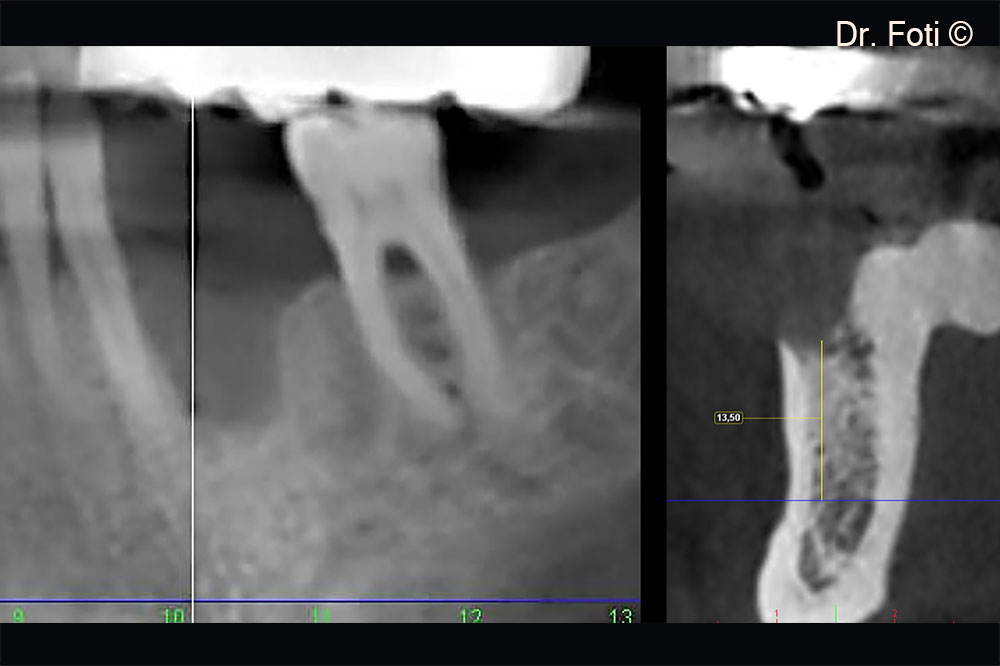

The CBCT scan revealed a vertical defect in position 34

The two-year follow-up CBCT shows a vertical bone gain of 6.90 mm